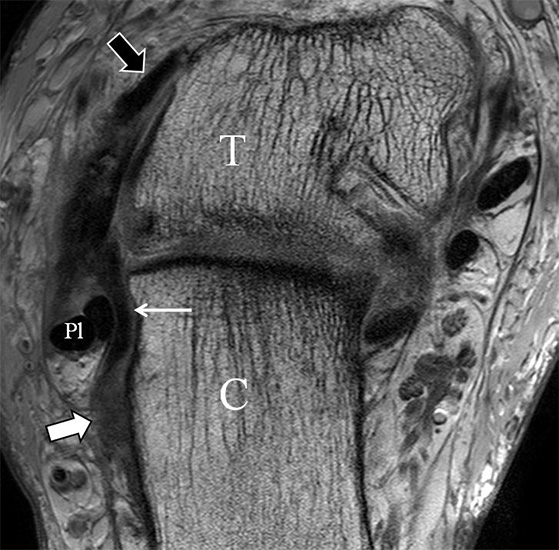

Das Ligamentum fibulotalare anterius entspricht einer bifaszikulären Struktur (Abb. 2 a) mit interponierendem fibrovaskulärem Gewebe (S. K. Sarrafian (ed). 2003). Es gibt jedoch Variationen der Ligamentanatomie. In 55% liegt das LFTA als bifaszikuläres Band (Abb. 2 a), in 9% als monofaszikuläre Bandstruktur (Abb. 2 b) und in 36% als multifaszikuläre, striäre Variante (Abb. 2 c) vor 3.

Das LFTA verbindet die antero-inferiore Fibulaspitze mit dem Processus lateralis tali und inseriert hier an einem oder zwei kleinen Tuberkeln 3. Der in Neutralposition horizontale Verlauf erleichtert die kernspintomographische Darstellung in dieser Standardebene. Das LFTA weist durchschnittlich eine Breite von knapp über 2 mm auf 4. Somit sind bei einer Routinedarstellung in 3 mm Schichtdicke Anschnittsphänomene, die die Diagnostik erschweren, regelmäßig anzutreffen. Dementsprechend sind auch die ligamentären Subfaszikel nicht zu differenzieren. In koronarer Darstellung ist dies aufgrund der hohen Auflösung in der Schichtebene jedoch möglich (Abb. 2 a-c), wobei hier wiederum eine Integritätsbeurteilung des Bandes erschwert ist. Unter Verwendung hochauflösender Techniken im Millimeterbereich (Schichtdicke) sind hingegen auch in der axialen Ebene die subfaszikulären Strukturen zu beurteilen (Abb. 3).